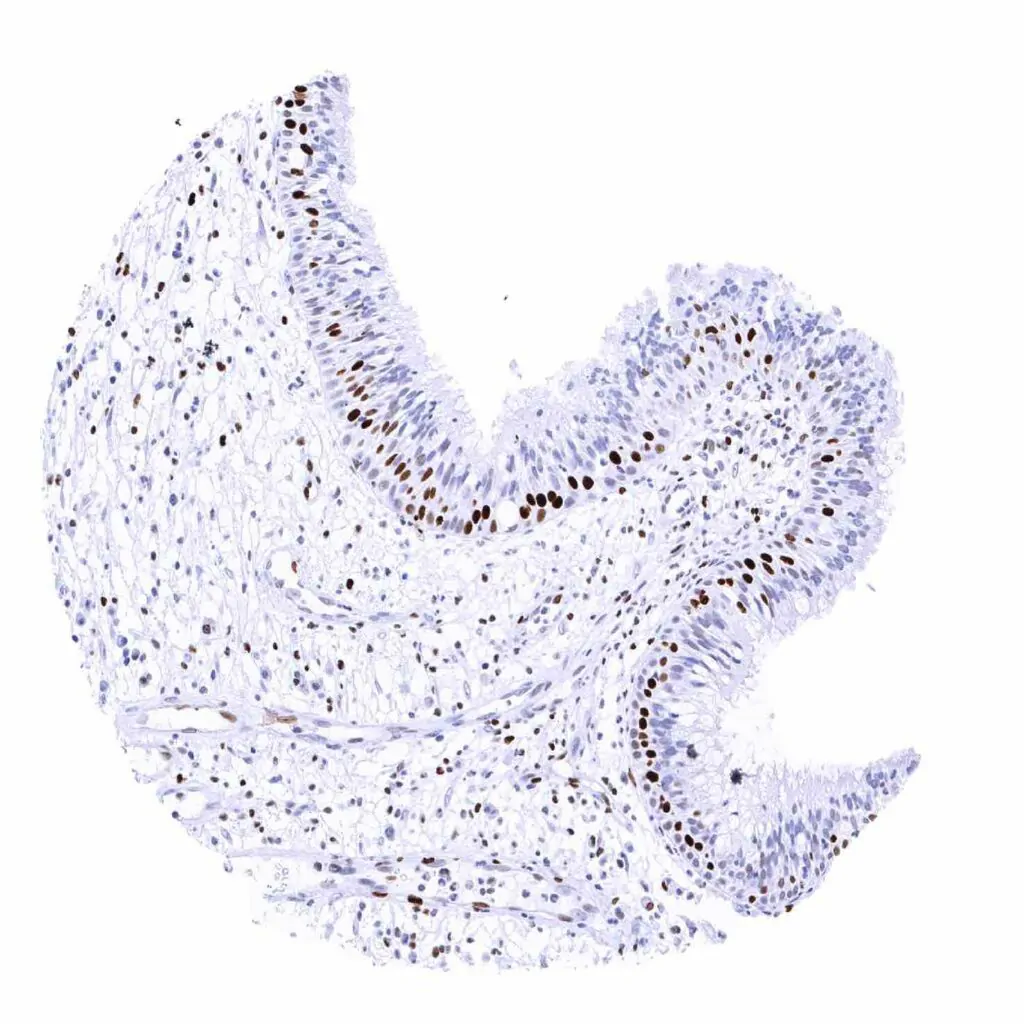

Appendix, mucosa – MCM2 staining predominates in in epithelial cells of the crypts. Some lymphocytes are also positive